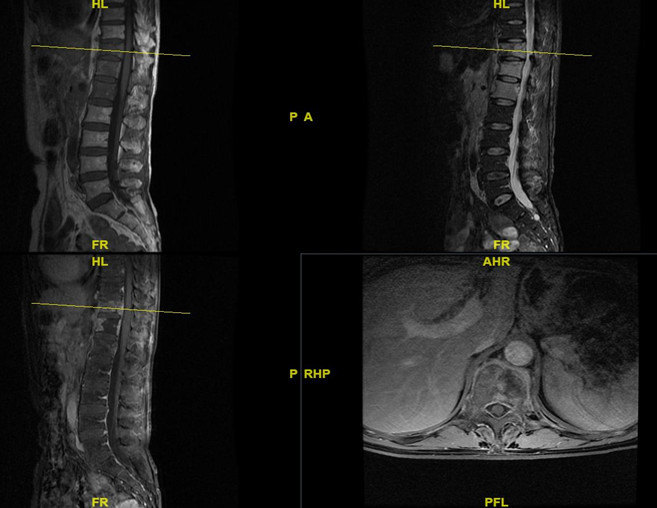

入院后,胸椎增强磁共振示胸6-8椎体层面椎管后缘梭形异常信号-考虑髓